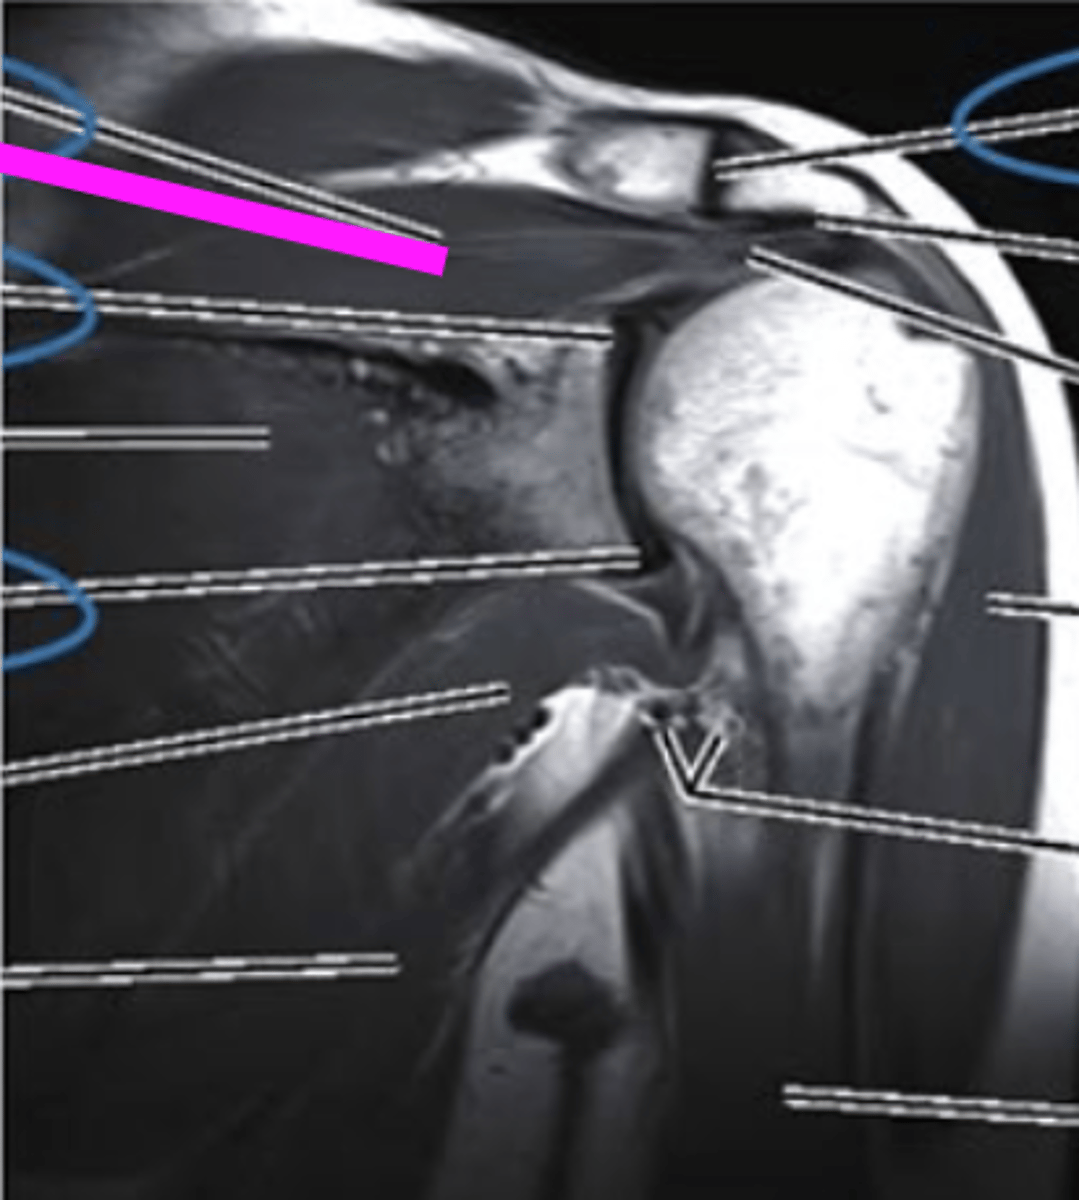

Sagittal MRI

what view is this and what imaging type?

acromion

what does the pink line point to?

supraspinatus muscle and tendon

coracoid process

the glenoid fossa